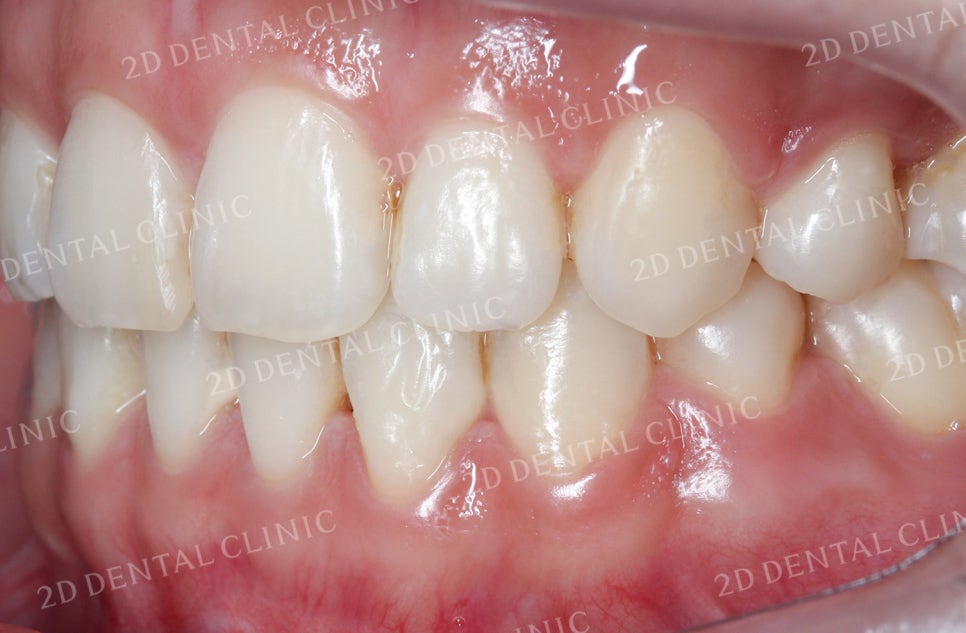

좌측의 안모 사진입니다.

치열의 총생으로 인해

송곳니 부근에 생겼던 틈들이

잘 덮혀진 모습입니다.